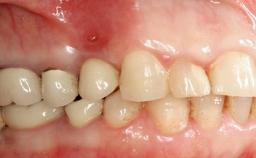

Peripheral Giant-cell Granuloma Associated with Peri-implant Tissues